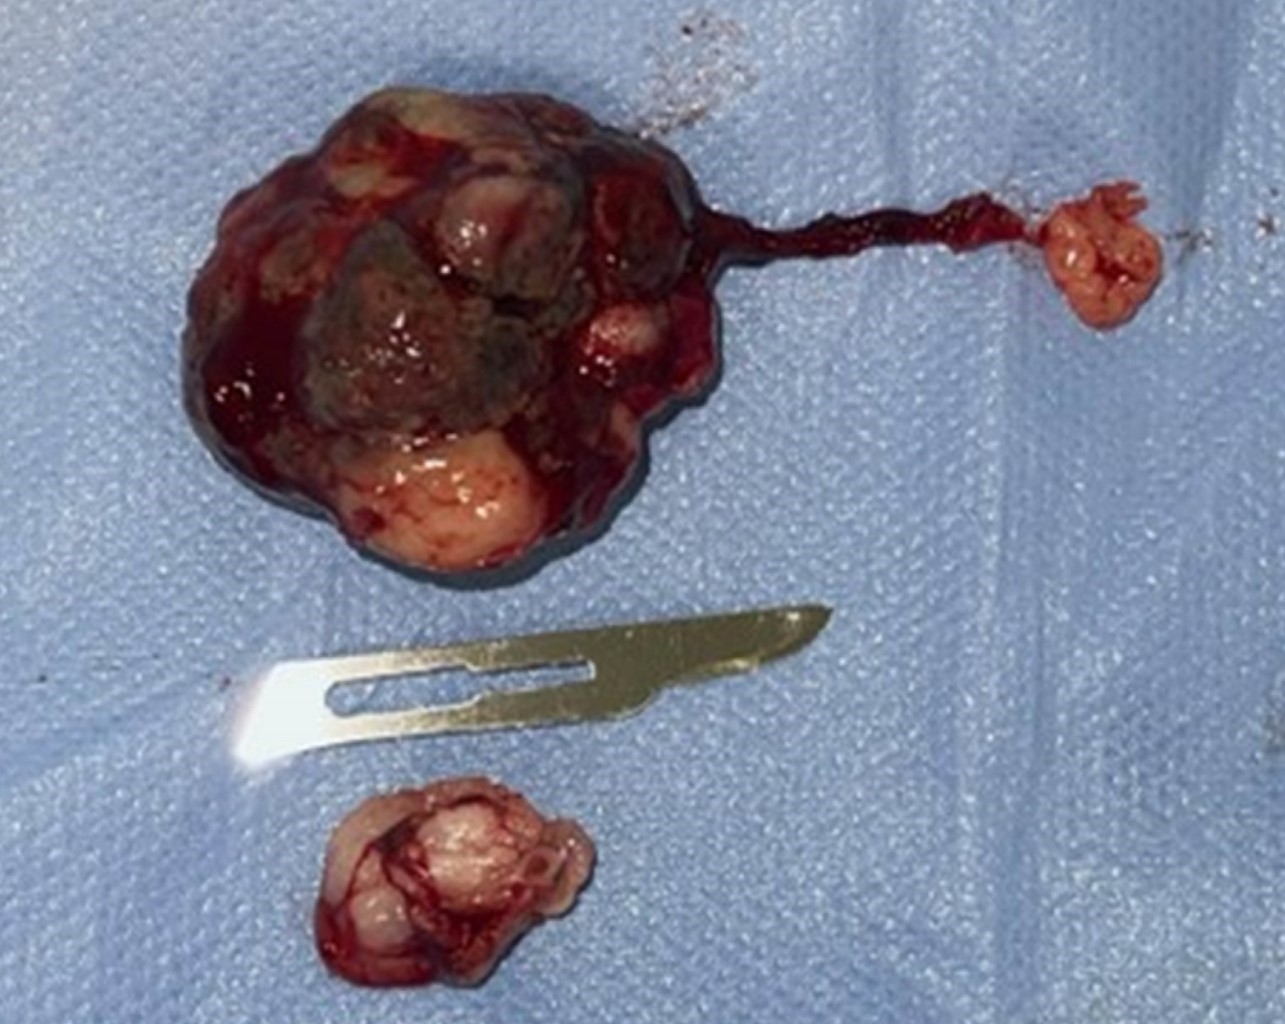

El 25 de mayo de 2025 se realizó el procedimiento exéresis de la lesión de más de 3 cm en relación a diente 4.8 (Figuras 4 y 5) bajo anestesia general sin complicaciones. En control del 23 de junio de 2025 se constata buena cicatrización y ausencia de recidiva. Se indica seguimiento periódico.

Figura 4

Figura 5